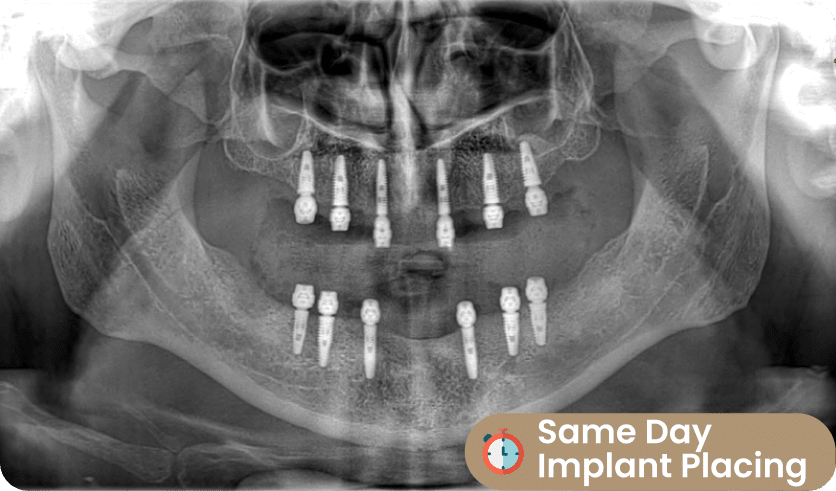

Implant Placing: Same Day (Day 1ST)

After 3D X-Ray process, Our dentists are starting to prepare teeth for the result. This steps can managed by several dentists in Dentafly. Cosmetic dentist shape teeth and prepare teeth for smile design process.